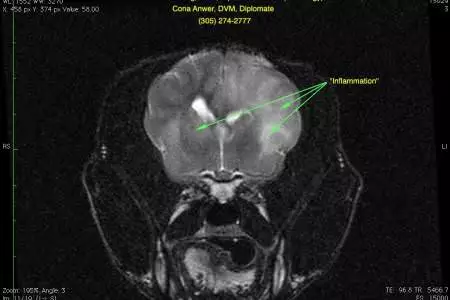

Based on Charlie’s examination, a problem affecting the left front part of the brain (cerebral cortex) was suspect. Magnetic resonance imaging (MRI) was performed. The first image is of Charlie’s head in profile. The nose is toward the left and the top of the head is toward the top of the picture. The second image is made 90 degrees to the other image as if Charlie’s nose was coming out of the computer screen. The right side of the picture is the left side of Charlie’s head. The brain is in the middle of the picture. The bright areas within the brain (arrows) represent inflammation, also called encephalitis.

Charlie scan